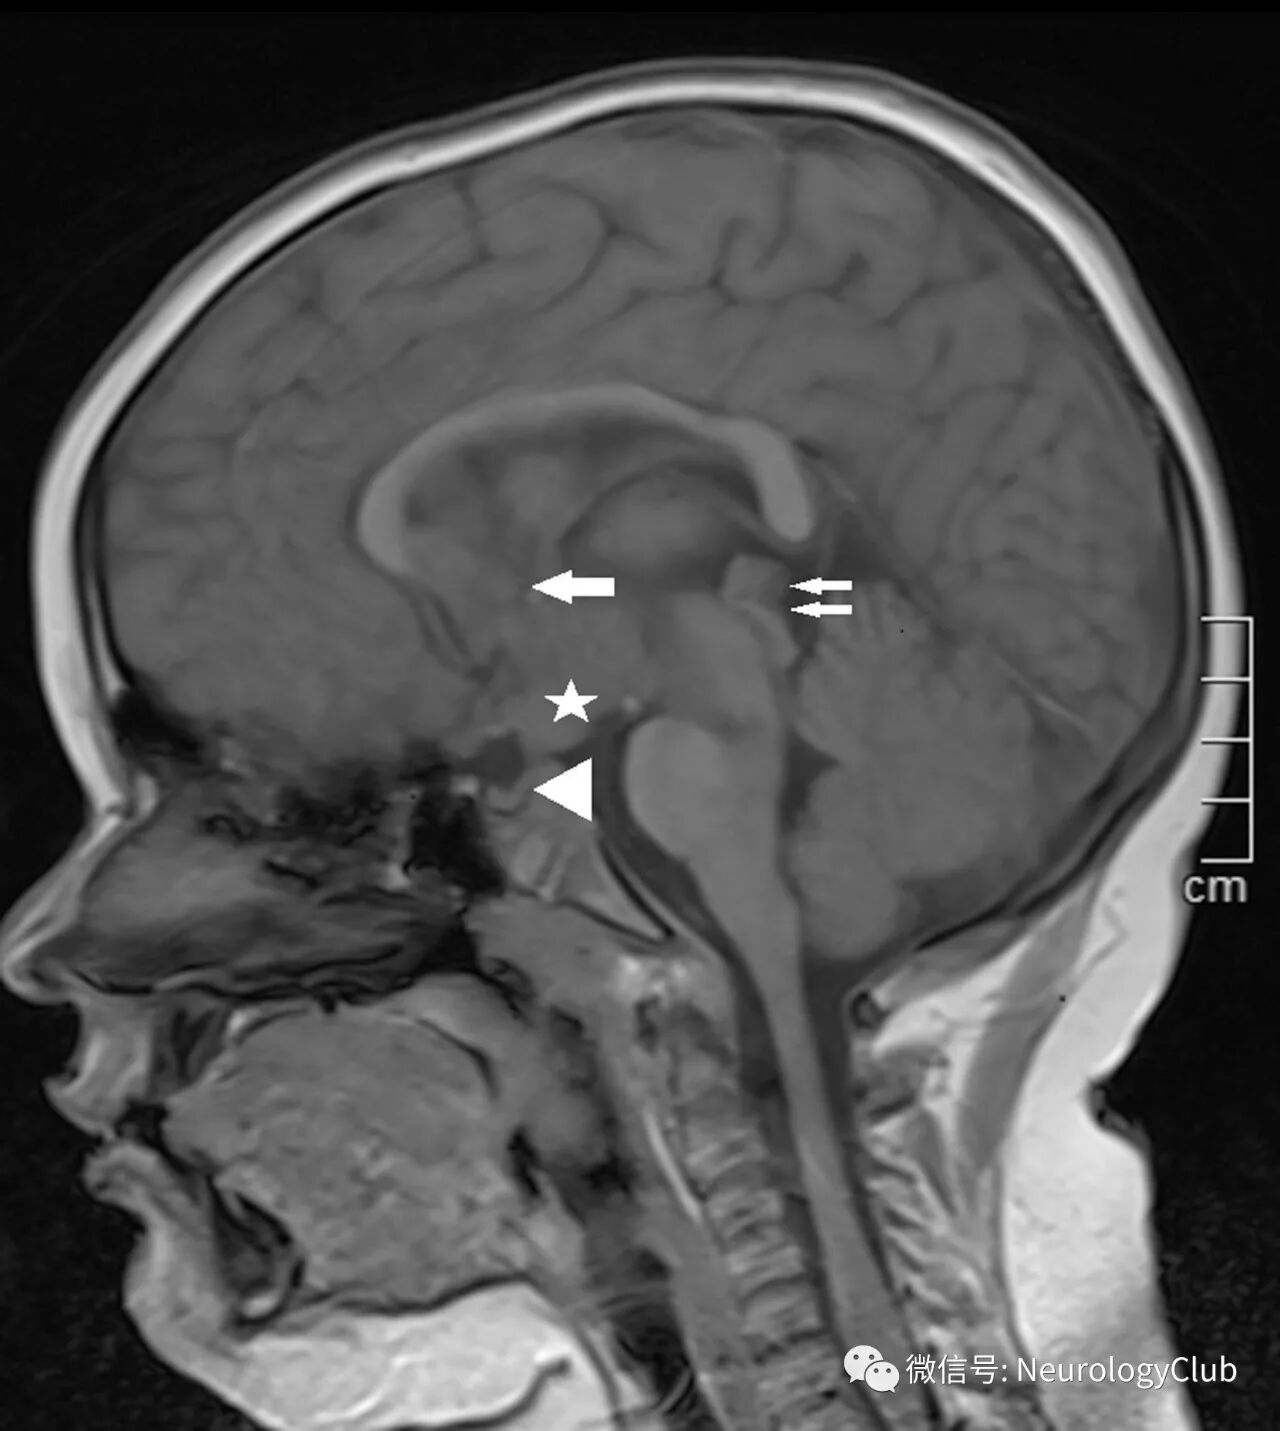

头颅MRI可见垂体柄增粗伴局限性下丘脑和松果体病变。此外T1WI上垂体后叶生理性高信号消失(图1)。FLAIR和T2WI可见脑白质广泛高信号和多发结节样病灶。增强后结节样病灶明显强化(图2)。未见骨性破坏。全身其他脏器影像学检查未发现异常。

(图1:矢状位T1WI可见垂体后叶生理性高信号消失[箭头]伴垂体柄增粗以及下丘脑[☆],胼胝体下[箭]和松果体[双箭]病变)